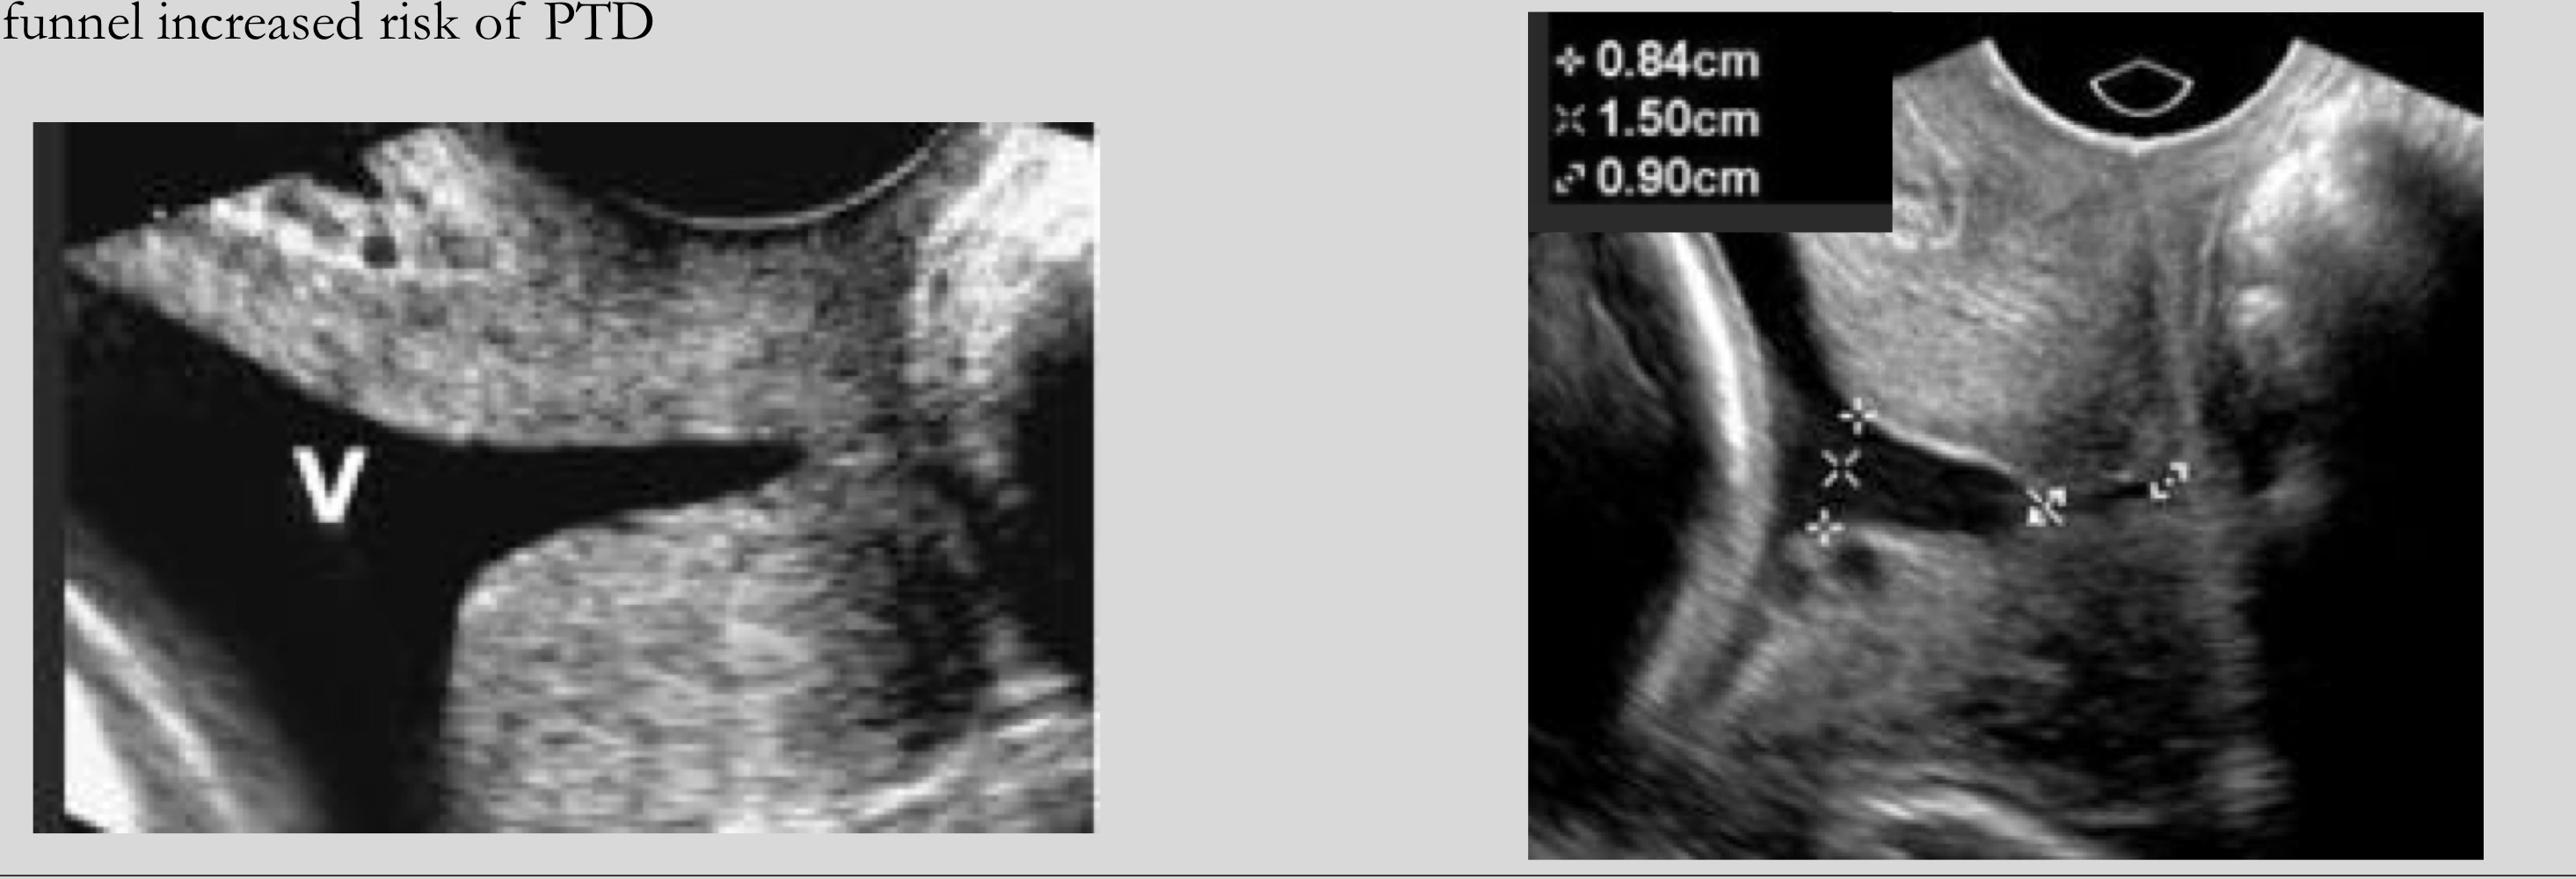

What is funneling

Dilatation of the internal os with shortening of cervical length

What shapes can funneling appear as

U-shaped or V-shaped

Which funnel shape is associated with higher risk of preterm delivery

U-shaped funnel

What is seen in severe cervical incompetence

Bulging (hourglassing) membranes into the vagina

What does hourglassing refer to

Membranes protruding through the cervix into the vagina